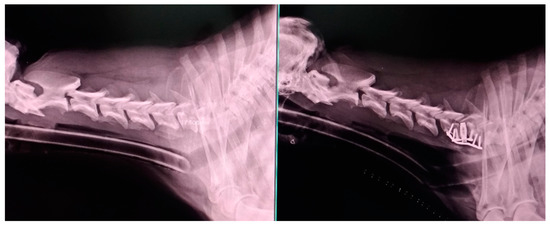

2.2. Surgical Technique